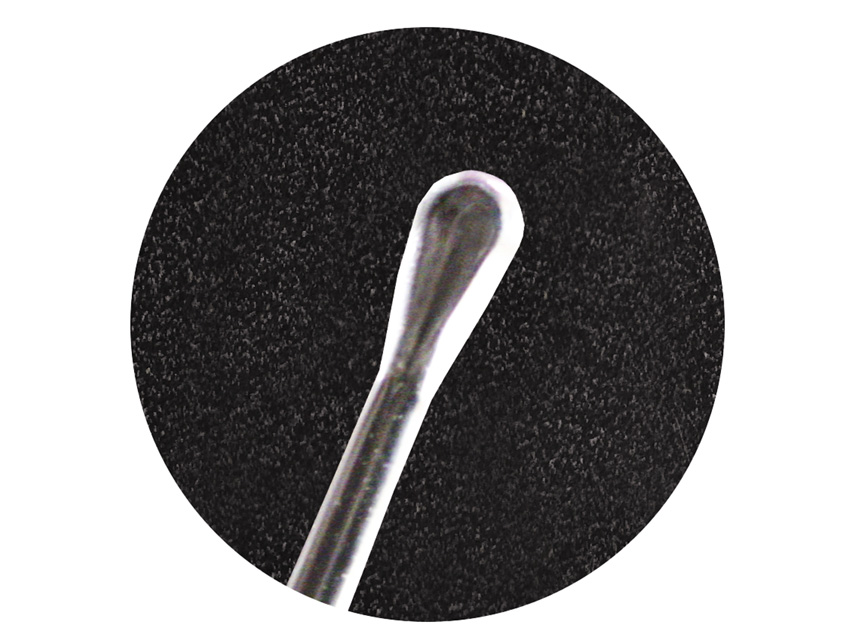

Φωτιζόμενες Κιουρέτες Αυτιών Bionix InfantScoop®

+30 6944162363Φωτιζόμενες Κιουρέτες Αυτιών Bionix InfantScoop® Bionix Lighted InfantScoop® #2260: Σχεδιασμένες με λεπτό άκρο 2mm, είναι κατάλληλες για χρήση σε βρέφη, ή μέσα από ένα, σχεδιασμένο γι αυτό το σκοπό, ωτοσκόπιο, όπως πχ το Ωτοσκόπιο Heine K100. Η Bionix έχει συνδυάσει την ασφάλεια των κιουρετών μιας χρήσης με μια ισχυρή φωτεινή πηγή LED και ένα φακό μεγέθυνσης. Με τον τρόπο αυτό οπτικοποίησε αυτό που συνήθως ήταν μια τυφλή διαδικασία. Αυτός ο σχεδιασμός σας δίνει τη δυνατότητα να χειριστεί ακόμα και τις πιο δύσκολες περιπτώσεις απομάκρυνσης της κυψελίδας με αυτοπεποίθηση και ασφάλεια. Οι φωτιζόμενες, με μεγεθυντικό φακό κιουρέτες, φωτίζουν τον ακουστικό πόρο εξαλείφοντας έτσι την πρακτική της τυφλής απόξεσης της ευαίσθητης περιοχής του αυτιού. Ολοκληρωμένο σύστημα διαχείρισης της κυψελίδας των αυτιών. Τα διαφορετικά είδη κιουρετών σας δίνουν τον πιο αποτελεσματικό, ασφαλή και οικονομικό τρόπο, αφαίρεσης κυψελίδας από τα αυτιά – ανεξαρτήτως μεγέθους αυτιού ή πυκνότητας της κυψελίδας. Άνεση & Ασφάλεια του ασθενή: Οι μεταλλικές κιουρέτες είναι κρύες, σκληρές και αιχμηρές. Οι κιουρέτες αυτιών Bionix με στρογγυλεμένες άκρες μειώνουν τον κίνδυνο τραυματισμού. Latex free: Ασφαλείς & υποαλλεργικές Αποτελεσματικότητα: Οι κιουρέτες αυτιών μπορούν να διπλασιάσουν την αποτελεσματικότητα των μεταλλικών κιουρετών, σε όλες τις περίπτωσεις, η δε πολυπροπυλενική σύνθεσή τους τις καθιστά σχεδόν άθραυστες. Αναλώσιμες: Οι κιουρέτες αυτιών δεν απαιτούν ακριβή και χρονοβόρα αποστείρωση ενώ παράλληλα περιορίζουν τον κίνδυνο επιμολύνσεων. Ευρεία Γκάμα: Διαθέσιμες σε έξι κωδικοποιημένα στυλ άκρης για να καλύψουν συγκεκριμένες ανάγκες, δίνοντάς σας «το σωστό εργαλείο για οποιαδήποτε εργασία» για κάθε περίπτωση. Η αναγραφόμενη τιμή αναφέρεται σε πακέτο (κιτ) το οποίο περιέχει 50 κιουρέτες για βρέφη/παιδιά (#2260), μια φωτεινή πηγή LED & ένα μεγεθυντικό φακό.